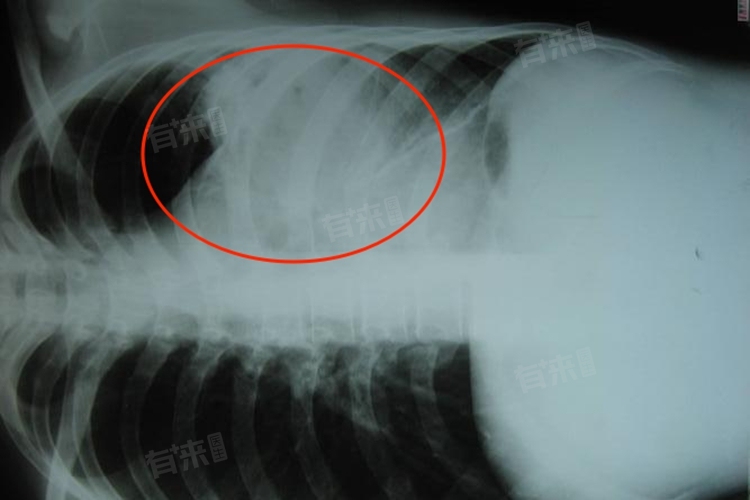

肺脓肿的症状表现多种多样,常见的症状主要包括高热、咳嗽、乏力、咳脓臭痰、咯血、胸痛、气急等。在出现肺脓肿症状时,患者应及时就医,以便查明原因并进行针对性治疗。

4、咳脓臭痰:7-10天后,咳嗽加剧,咳出大量脓臭痰。脓肿破溃于支气管,大量脓液和坏死组织被咳出,同时厌氧菌感染导致痰液有臭味。

7、气急:肺脓肿破溃到胸膜腔,可出现突发性胸痛、气急。脓气胸的形成导致肺部功能受限,影响呼吸。